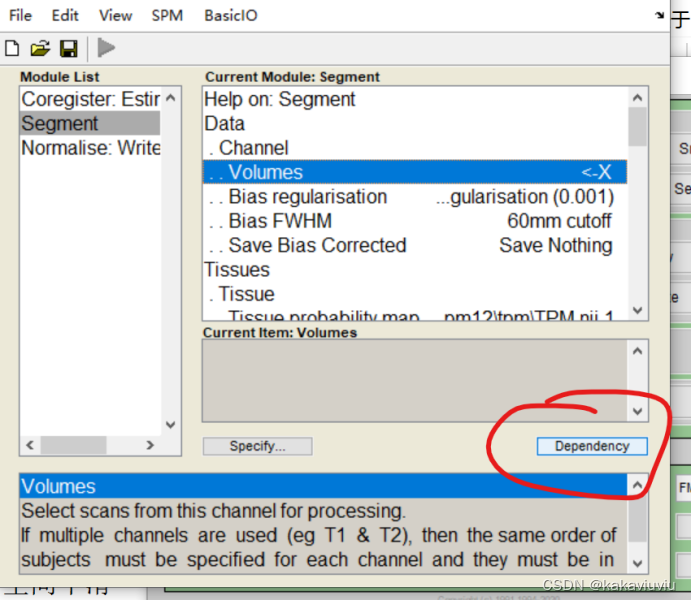

点dependency